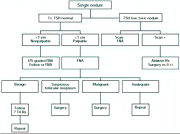

| 09:30, 7 בנובמבר 2012 | פאוכרומוציטומה714.png (קובץ) |  |

225 קילו־בייטים | Motyk | 1 | |